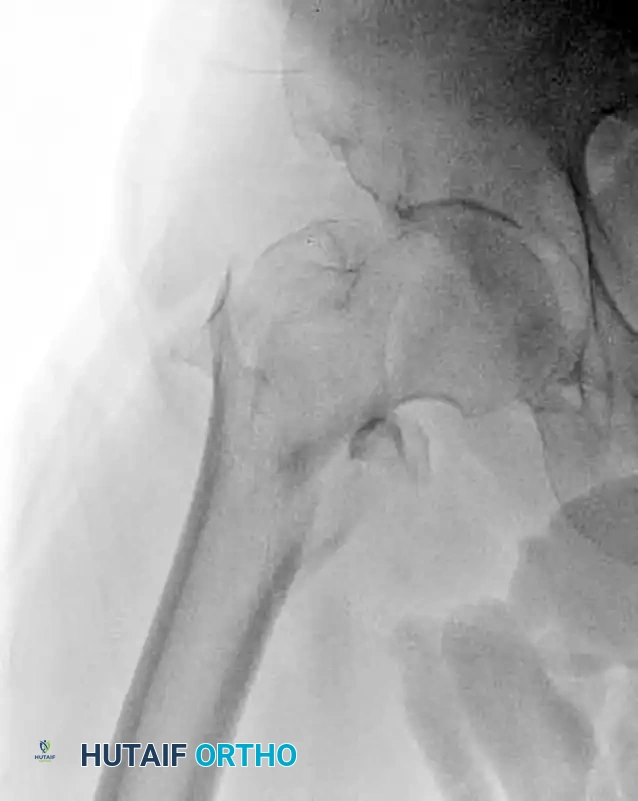

Preoperative anteroposterior radiograph demonstrating an unstable intertrochanteric femoral fracture, an ideal indication for the InterTAN device.

Intertrochanteric femoral fractures represent a significant portion of the fragility fractures encountered by orthopedic surgeons. While stable fracture patterns (OTA/AO 31-A1) may be adequately managed with a sliding hip screw (SHS), unstable patterns—including reverse obliquity fractures, fractures with subtrochanteric extension, and those with compromised lateral femoral walls (OTA/AO 31-A2 and 31-A3)—demand the biomechanical advantages of a cephalomedullary nail.